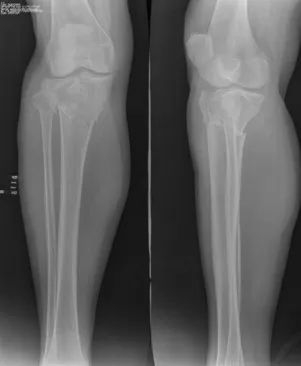

X光片

“当时比较幸运的是,医院保存了王秀芝案发时拍摄的双腿CT电子数据。这些数据很完整,是我们三维建模的关键。我先给王秀芝的右腿构建了损伤后的模型,然后再利用其左腿的数据用镜像(对称反转)的方式构建了右腿损伤前的三维有限元模型。”李正东说。